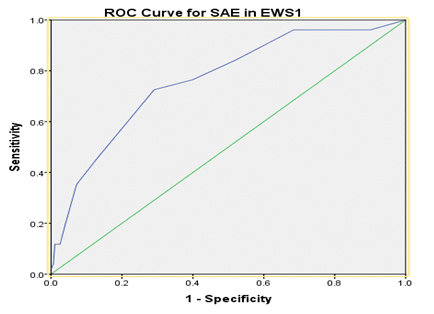

Emergency Medicine | Oct 14, 2024

The Utility of Early Warning Score (EWS) in Predicting Serious Adverse Events Among Patients Presenting to Emergency Departments of Muhimbili National Hospital and MUHAS Academic Medical Center

Background: Early Warning Scores (EWS) have been widely studied and applied in high-income countries (HIC) for more than a decade,...Read More